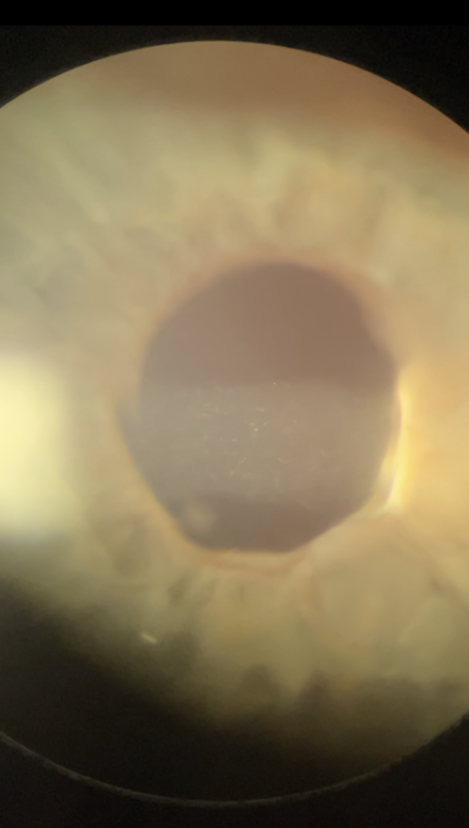

On slit lamp exam, Cell and flare is visible in the left anterior chamber, and the lens is not identifiable in the posterior chamber.

Figure 4. On slit lamp exam, Cell and flare is visible in the left anterior chamber, and the lens is not identifiable in the posterior chamber.